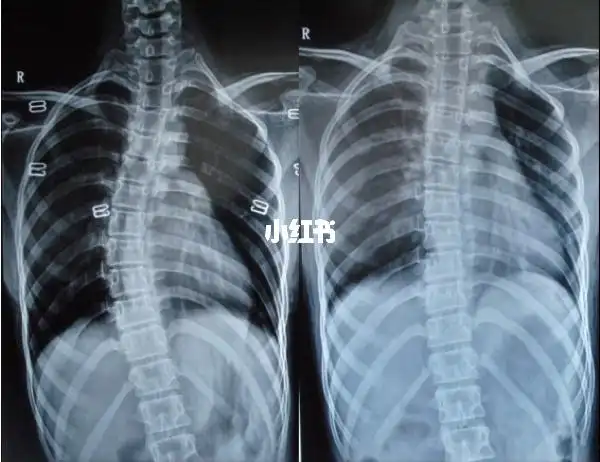

新苗脊柱侧弯医体治疗体系4060度治疗好转的病例

脊柱侧弯少年的改变

特发性脊柱侧弯患者今年夏天终于可以穿裙子了